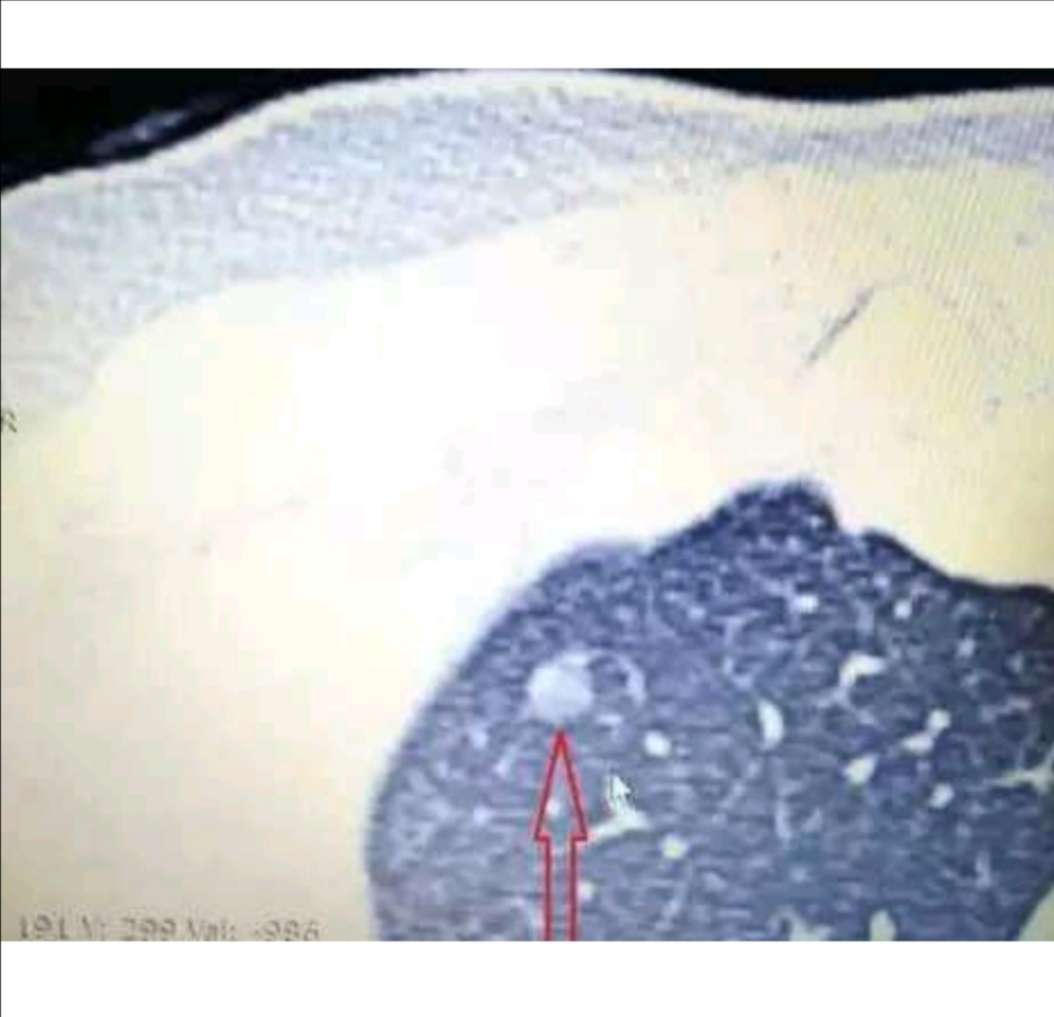

下图配上典型的实性结节和磨玻璃结节,供大家参考。

图片1:典型的肺胸膜下实性结节,为慢性炎症灶

图片2:典型的肺磨玻璃结节(GGN),为早期肺腺癌